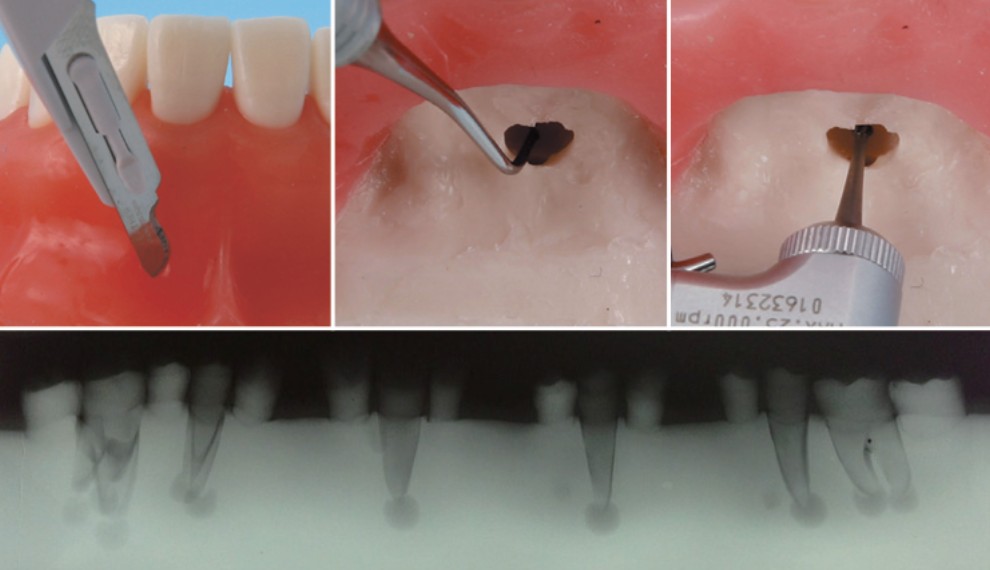

Apicoectomy Practice Model (SUG1009-T-SP)

– แบบจำลองใช้สำหรับฝึกทำศัลยกรรมปลายรากฟัน มีการจำลองการบาดเจ็บที่ปลายรากฟัน ด้านขวาของแบบจำลองมีฟันซี่ #11, #24, #26 ด้านซ้ายแบบจำลองมีฟันซี่ #35, #36, #44

- ฟันซี่ #11 มี 1 ช่องราก, #24 มี 2 ช่องราก และ #26 มี 3 ช่องราก

- ฟันซี่ #35 มี 1 ช่องราก, #36 มี 2 ช่องราก และ #44 มี 1 ช่องราก